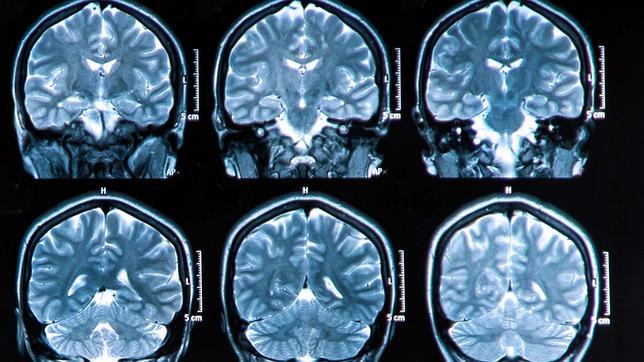

Sin síntomas, pero aquellas personas cuyos progenitores tienen o han tenido alzhéimer, los dos, pueden mostrar signos de la enfermedad en el cerebro décadas antes de que aparezcan los síntomas. Un estudio que se publica en « Neurology » señala que dichos signos puede ser identificados ... mediante un escáner cerebral.

Los investigadores han analizado a 52 personas, entre 32 y 72 años de edad, y sin demencia que fueron sometidos a varios tipos de pruebas de imagen cerebrales, incluyendo -Tomografía por Emisión de Positrones (PET) y resonancia magnética (RM). Mientras que el PET mide la cantidad de placas cerebrales y la actividad general del cerebro, como el metabolismo cerebral, la RM analiza la estructura del cerebro y las posibles reducciones en el volumen cerebral.